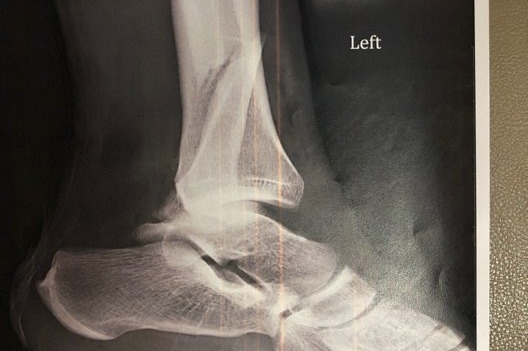

His left ankle bone was out.

After breaking the line, he got tackled from behind and the force dislocated his ankle, fractured his fibula and shredded multiple ligaments.